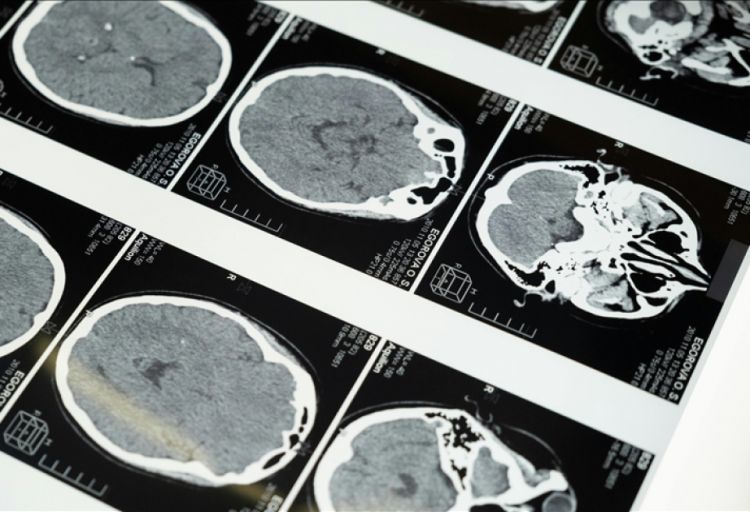

Biruni Universiteti Xəstəxanası nevrologiya mütəxəssisi professor Talip Asil insult və onun əlamətləri ilə bağlı əhəmiyyətli xəbərdarlıqlar edib. Xəstəxanadan verilən açıqlamada bildirilib ki, insult dünyada üçüncü əsas ölüm səbəbidir və bunun üzün ani yerdəyişməsi, qol və ya ayaqda zəiflik kimi əlamətləri görünə bilər. Əlamətlər arasında nitq pozğunluğu da yer alır.

NUHÇIXAN Anadolu Agentliyinə istinadla xəbər verir ki, professor T.Asil, bu simptomların müşahidə edildiyi hallarda vaxt itirilməməsinin vacib olduğunu vurğulayıb. O bildirib ki, insult dünyada əhəmiyyətli ölüm və əlillik səbəbidir. Professor, ictimaiyyəti bu məsələdə daha diqqətli olmağa çağırıb.

İnsultun yaş, cins, genetik və irq kimi müxtəlif faktorlara görə inkişaf edə biləcəyini qeyd edən T.Asil, insult riskinin 55 yaşdan yuxarı insanlarda daha yüksək olduğunu, lakin daha gənc yaşlarda kişilərdə də bu riskin mövcud olduğunu bildirib: “Diabet, hipertoniya, piylənmə, yüksək xolesterin və ürək xəstəlikləri olan insanlarda insult riski artır. Erkən müdaxilə insultun qalıcı zərər verməsinin qarşısını ala bilər. Son 20 ildə insult müalicəsində əhəmiyyətli irəliləyişlər əldə edilib. Damar tıxanmaları nəticəsində yaranan insult erkən mərhələdə müalicəsi mümkün olan xəstəlik halına gəlib. Beyində tıxanmış damarlar dərmanlar və anjioqrafik üsullarla açıla, beləliklə xəstənin şikayətləri qismən və ya tamamilə həll edilə bilər. Ən kritik element müdaxilənin həyata keçirilməsidir. Bu məlumatlar, ictimaiyyətin insultun əlamətləri və risk faktorları haqqında məlumatlılığını artırmaq məqsədini daşıyır.